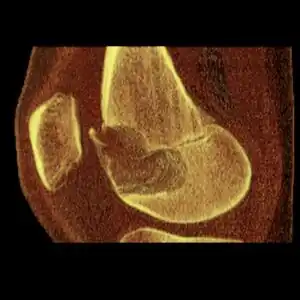

| Cancerous (Chondrosarcoma) | Conventional chondrosarcoma grade I (axial skeleton)-III[1][2] | ![]() |